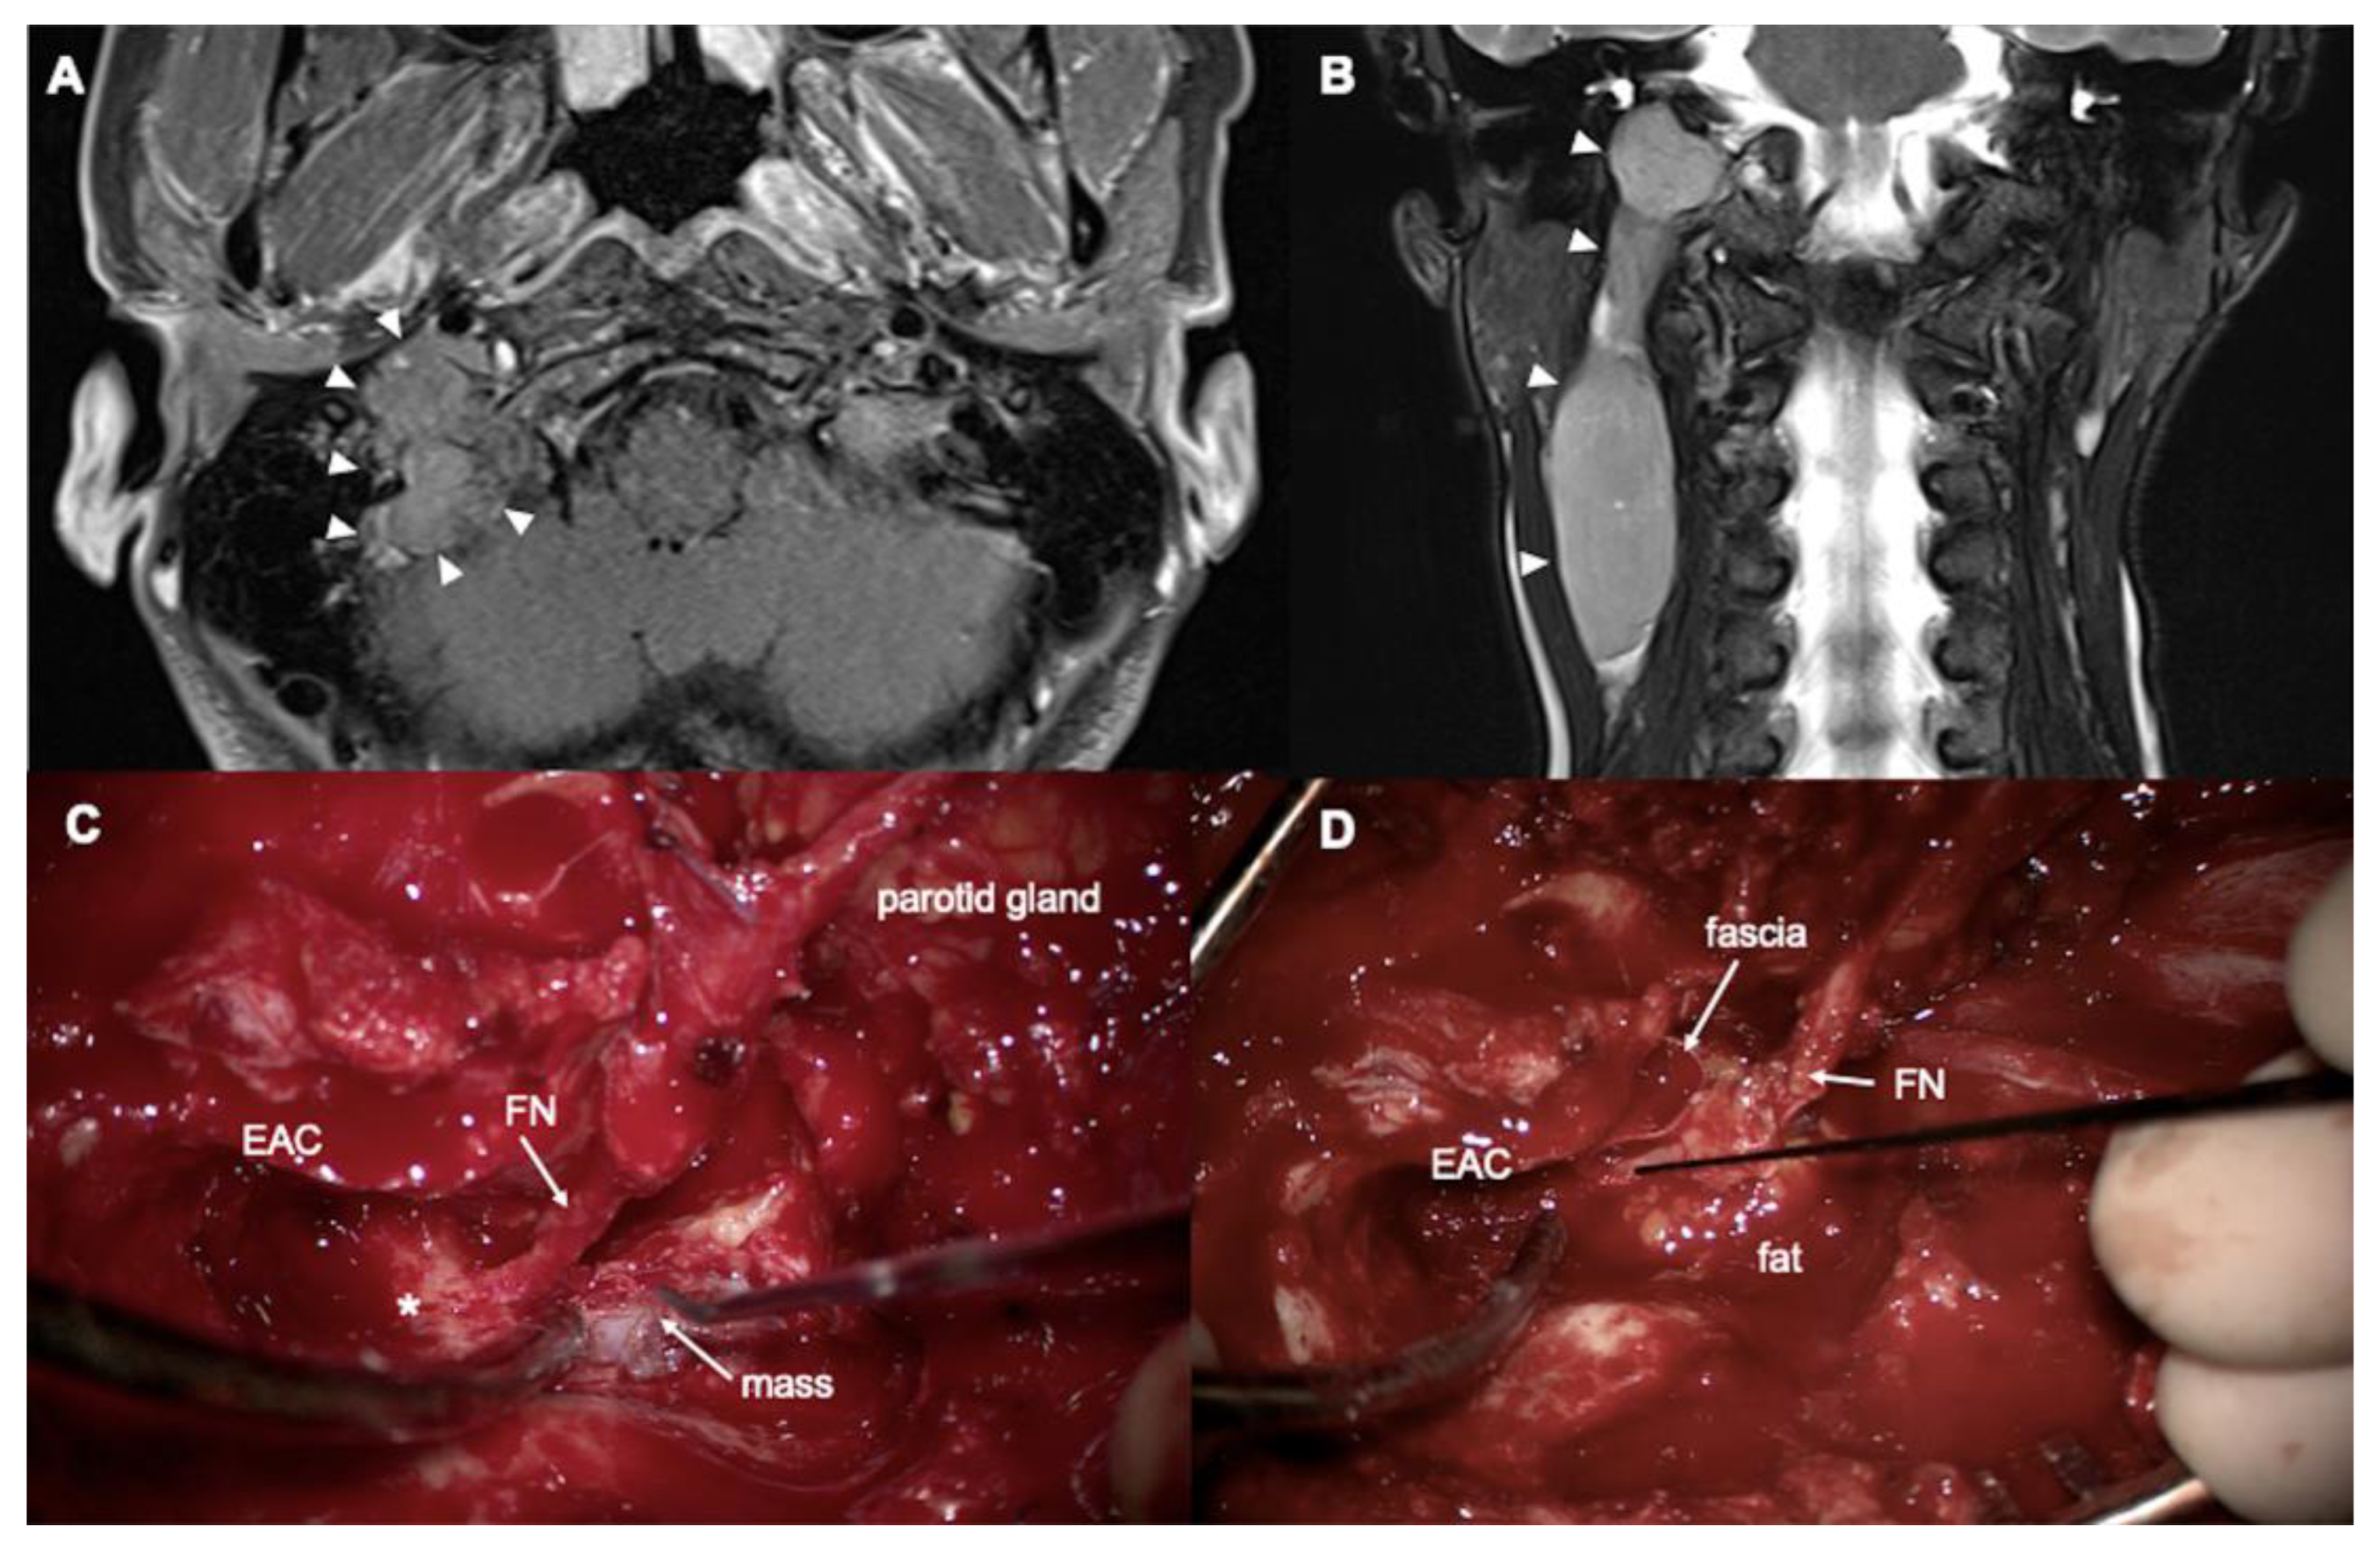

A 42-year-old woman presented with right-sided tinnitus, otalgia, and a palpable neck mass. Tympanic endoscopy revealed a clear right tympanic membrane. CT and MRI demonstrated an approximately 9.1 cm sausage-like intravascular mass in the right internal jugular vein, extending from the jugular foramen to the level III neck, consistent with a diagnosis of paraganglioma (Figure 3A,B). Preoperatively, the patient exhibited normal hearing without an ABG and showed no signs of facial palsy. Tumor embolization was performed preoperatively via the right ascending pharyngeal artery, occipital artery, and posterior auricular artery.

After performing a complete canal wall-up mastoidectomy and posterior tympanotomy while preserving the posterior EAC, the mastoid segment of the facial nerve was fully exposed through drilling. Following partial superficial parotidectomy, neck dissection, and mastoid tip removal, the facial nerve was partially rerouted anteriorly (“short” rerouting). The entire tumor, extending from the jugular bulb to the internal jugular vein, was then identified (Figure 3C). The jugular bulb was opened, and bleeding control was achieved at the inferior petrosal sinus. After ligating the right internal jugular vein, the tumor was removed while maintaining bleeding control throughout the procedure. The partially rerouted facial nerve was subsequently repositioned, and the mastoid cavity was obliterated with an abdominal fat graft (Figure 3D). Histological examination confirmed the diagnosis of angioinvasive paraganglioma. Owing to the tumor’s extensive intravascular growth, the patient underwent adjuvant radiotherapy. Postoperative hearing measurements showed an ABG of 8.75 dB HL and an air conduction PTA of 22.5 dB HL. A follow-up MRI at 2.5 years after surgery showed no evidence of tumor recurrence.

Figure 3. A 42-year-old woman with angioinvasive paraganglioma. (A) Axial T1- and (B) coronal T2-weighted MRI show a mass from jugular foramen to right neck (arrowheads). (C,D) Intraoperative findings. arrowheads: mass, EAC: external auditory canal, FN: facial nerve, * lateral semicircular canal.